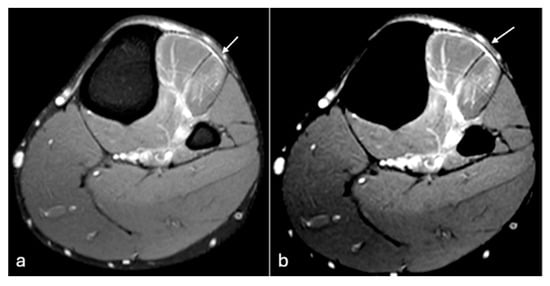

Figure 5. PDFS axial MR images of the left thigh (a,b). Soft tissue oedema changes seen in vastus medialis (arrow) are better delineated on default window image (a) in comparison to modified windowing (b). W/L of the image (a)—1804/851, (b)—902/930.